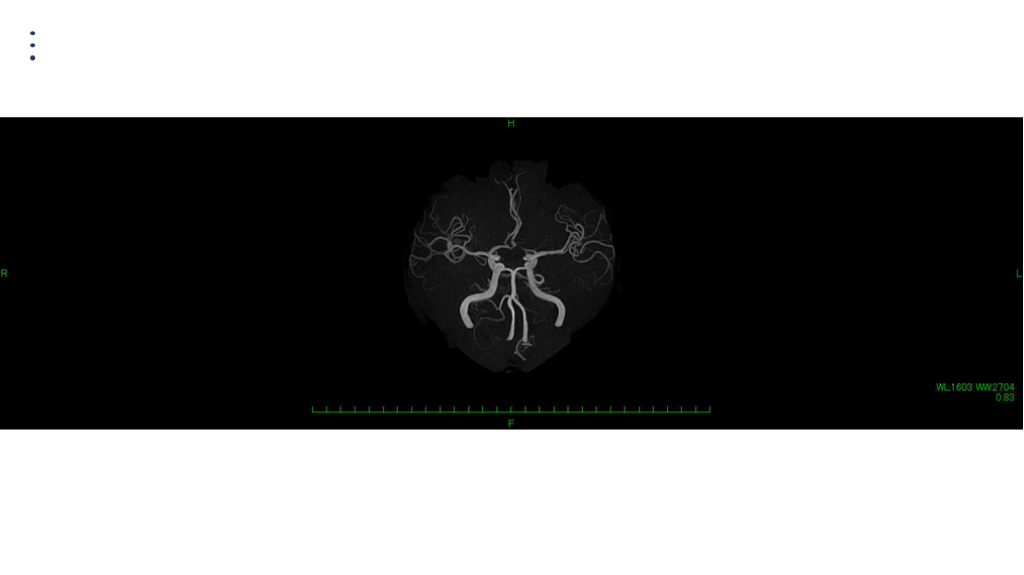

画像 所見 DAY 30 MRA 改善